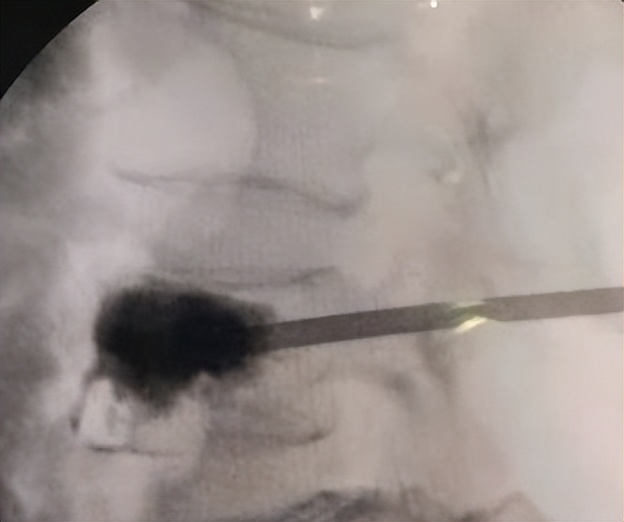

填充骨水泥